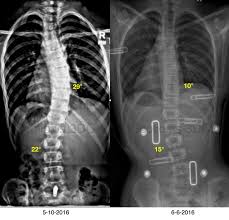

Best Of Curves twists and bends a practical guide to pilates for scoliosis EBook Images